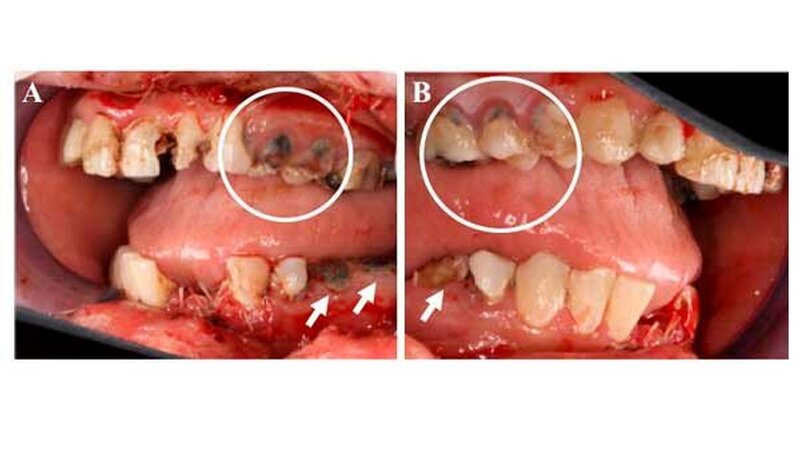

Die weitere klinische Inspektion ergab intraoral den Befund eines kariös tief zerstörten Restzahngebisses mit multiplen, teils gelockerten, nicht erhaltungswürdigen Zähnen.

Einige Tage später stellte sich die Patientin erneut in unserer Ambulanz mit einer ausgeprägten Wundheilungsstörung, einer beginnenden Superinfektion sowie einer beginnenden Weichgewebenekrose vor.

) erfolgte in Vollnarkose eine Wundrevision und Reposition der Nasenbeinfraktur. Zusätzlich erfolgte - mit Ausnahme der dentes caninii - die operative Entfernung der tief zerstörten und nicht erhaltungswürdigen Restbezahnung des Ober- und Unterkiefers in Kombination mit einer modellierenden Osteotomie sowie einem plastischen, speicheldichten Wundverschluss.

), weiche Kost und Prothesenkarenz. Die histopathologische Aufarbeitung der entnommenen Knochenproben zeigte Anteile von nekrotischem Knochen, obwohl weder in der klinischen Inspektion, noch in der Bildgebung (OPG und CT) Anzeichen für eine Knochennekrose zu finden waren.